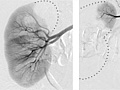

An angiogram is an X-ray test that uses dye and a camera to take pictures of the blood flow in an artery or a vein. An angiogram can be used to look at the arteries or veins in the head, arms, legs, chest, back, or belly. This test is done to look for problems in the arteries or veins.

During an angiogram, the doctor will put a thin, flexible tube into a blood vessel in your groin or arm. This tube is called a catheter. The doctor guides the tube to the blood vessel that will be studied. Then a dye is injected through the tube to make the area easier to see. X-rays or pictures are taken of the area.

When the catheter is in place, the dye is injected through it. You may be asked to take a breath and hold it for several seconds. Several X-ray pictures will be taken one after another. These will be available right away for your doctor to look at. You need to lie very still so the pictures are clear. More pictures may be taken.

Normal:

- The blood vessels are normal in shape, size, location, and number.

- The dye flows evenly through the blood vessels.

- No narrowing, blockage, bulging, or other problem of the blood vessels is seen.